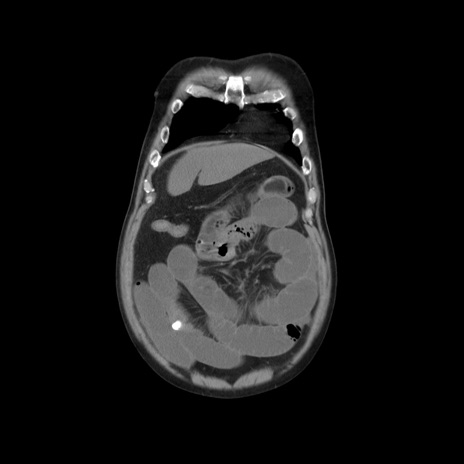

横断像

【症例】 60歳代男性

【主訴】 腹部膨満、嘔吐

【現病歴】5日前頃より倦怠感を認め食事量減少し4日前の朝嘔吐、食事摂取困難となった。 3日前近医受診し点滴施行され整腸剤などを処方された。 当日他院を受診し、腹部膨満著明、炎症反応の上昇(CRP10.8、WBC11200)あり、紹介受診となる。

【身体所見】 意識JCS1 受け答えがはっきりしないBP 111/57mHg、 P 67bpm、、BT35.2°C、SpO2 97%(RA)、 腹部:膨隆、打診で鼓音あり、全体的に圧痛有り、腸蠕動音(-)、反跳痛ははっきりせず。

【データ】WBC 11400、CRP 14.20